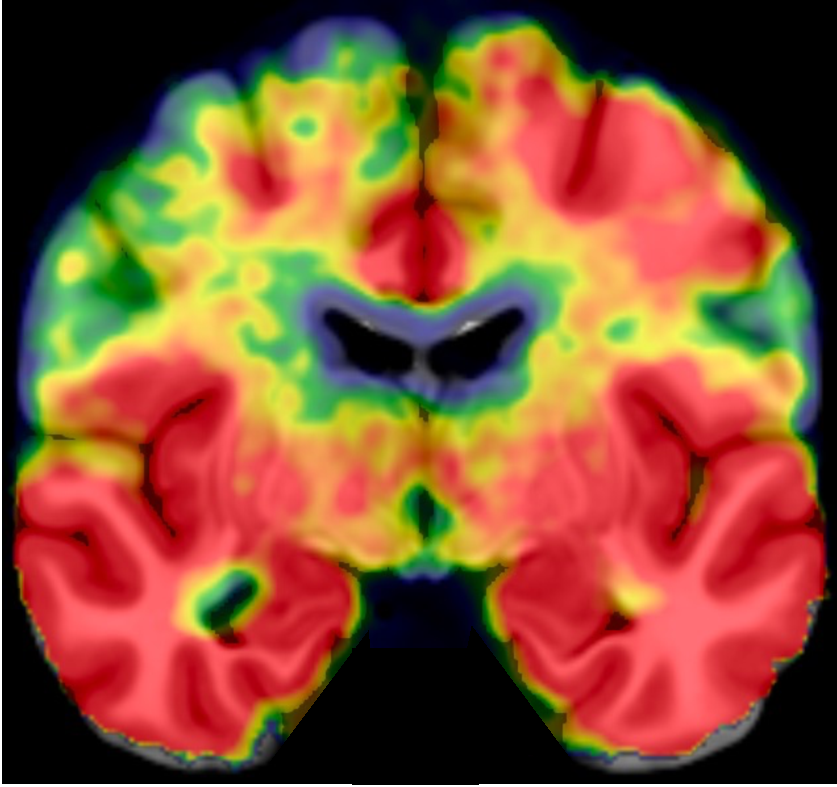

【C期(中期)】

• 表现:核心1阳性,Tau扩散到新皮层,中等量沉积

• 意味着:病变范围扩大,影响多个认知域